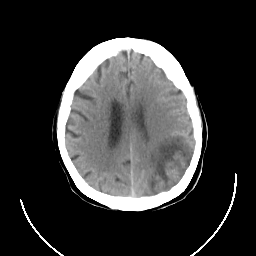

CT Study #3 -- Slice #19

[Home][Help][Clinical][Tour 1] Slice 19